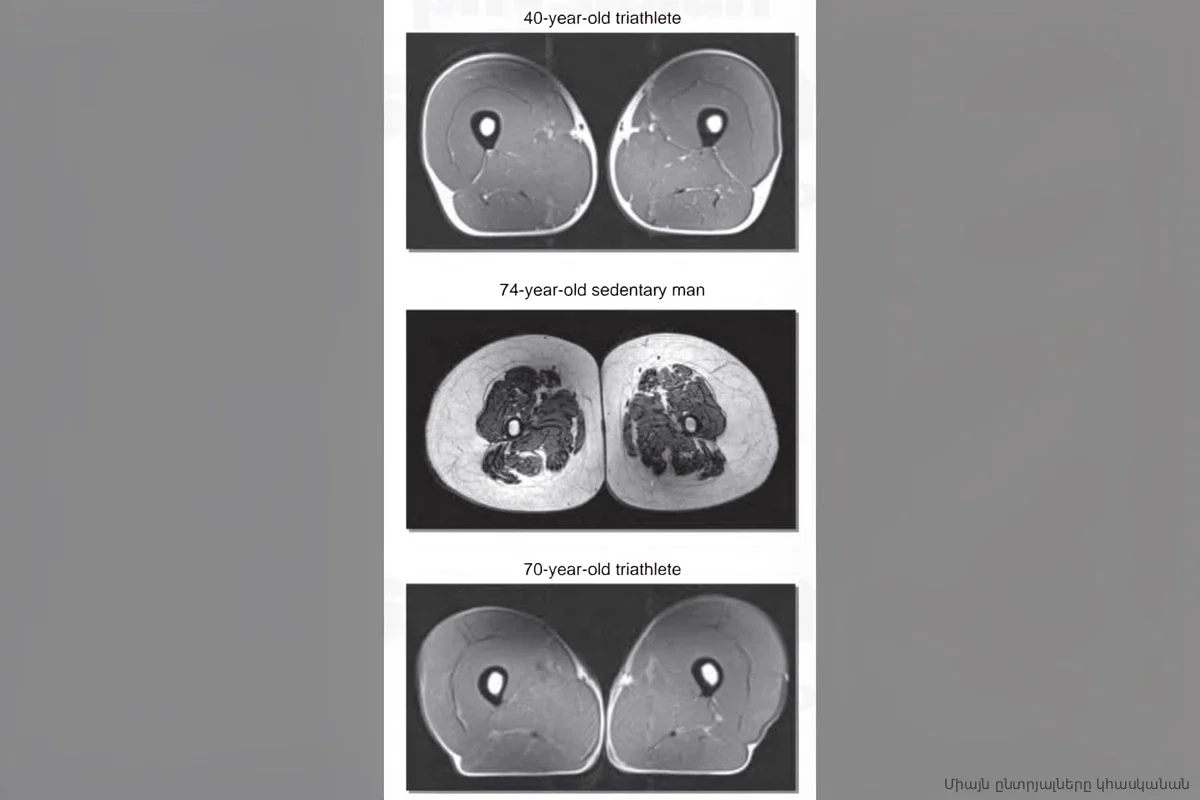

МРТ показало, во что превращаются мышцы от фастфуда даже при регулярных тренировках

Узнайте, как ультрапереработанная еда вызывает жир внутри мышц даже при тренировках. МРТ показало риски остеоартрита и слабости суставов.